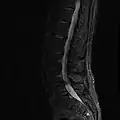

MRI lumbar spine with degeneration (sagittal FAST STIR)- MRI lumbar spine pre-hemilaminectomy (sagittal T2 FRFSE)